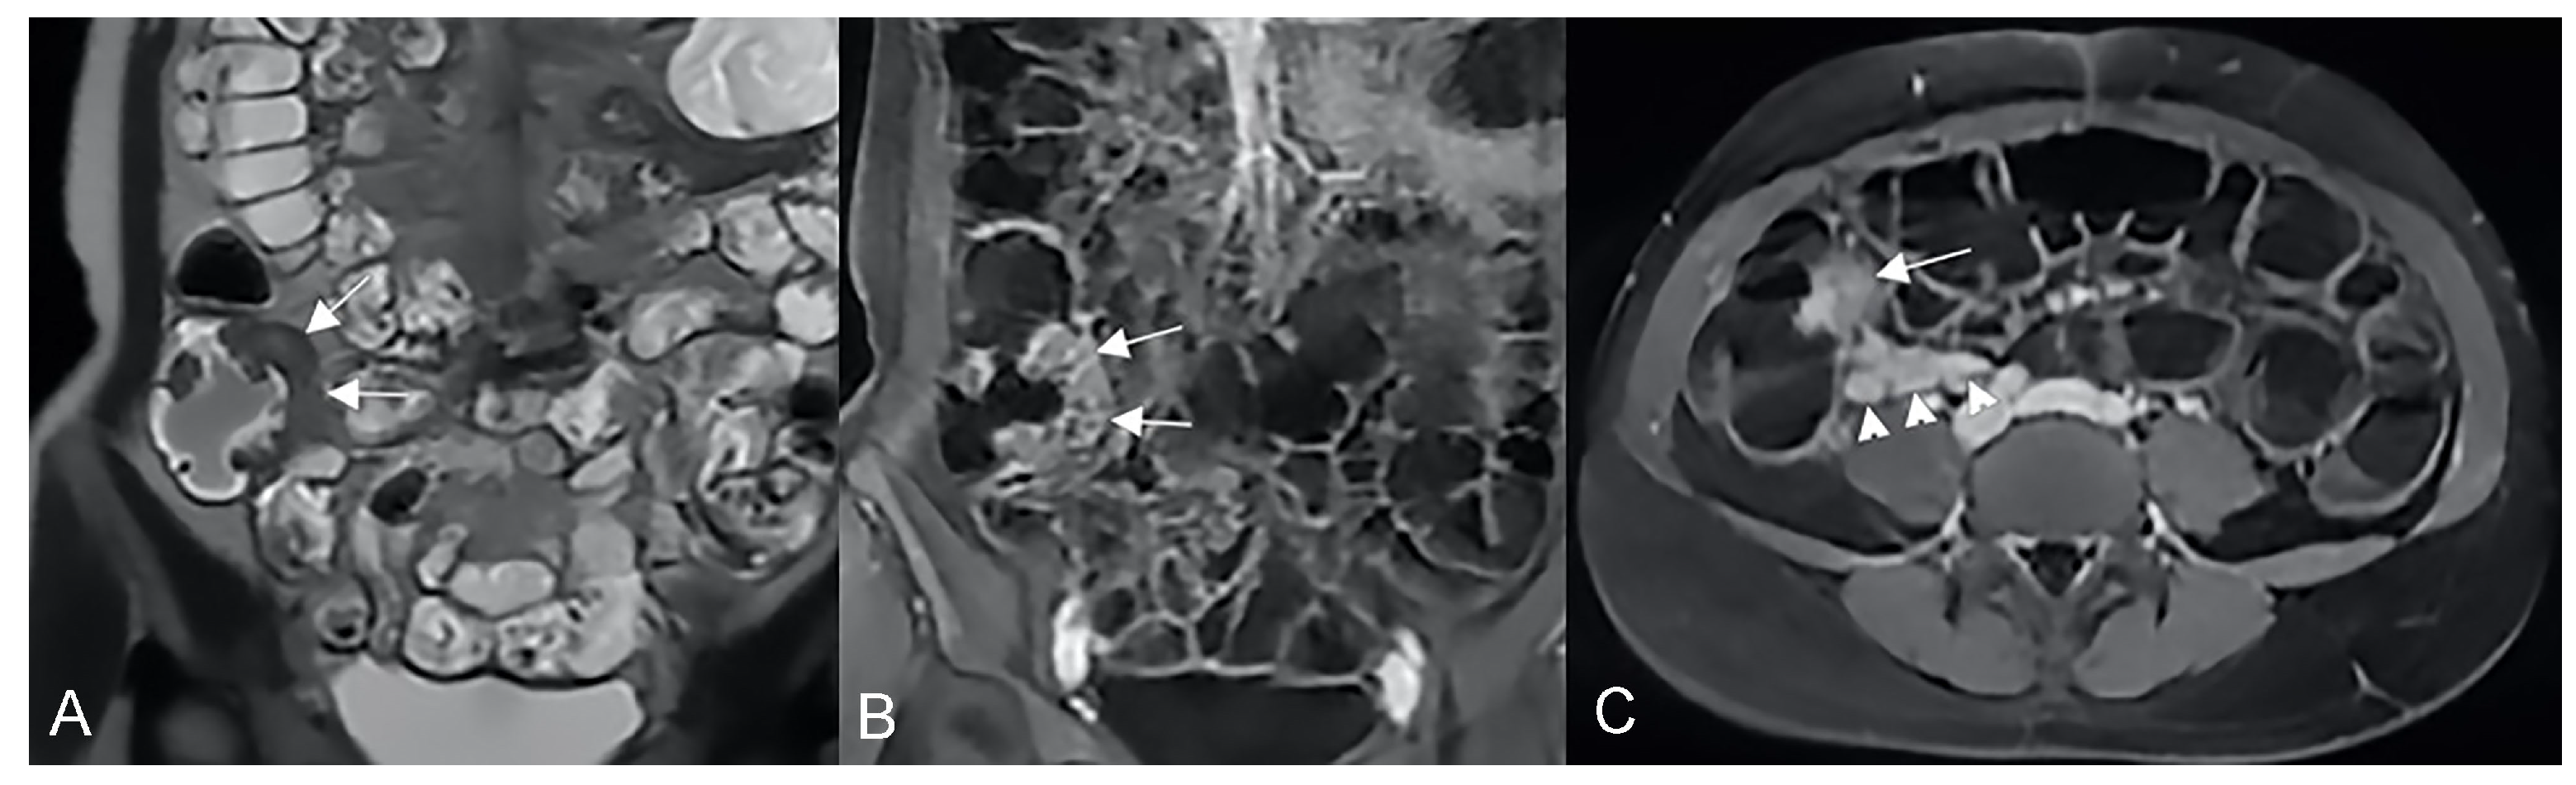

An abdominal phlegmon is an obsolete term that refers to an inflammatory mass that can develop in the setting of penetrating Crohn’s disease. The term phlegmon is ambiguous and relates to an ill-defined inflammatory dense mesenteric mass. It typically spreads without a well-defined wall and involves the mesentery and adjacent bowel with fistula or abscess as possible complication [12]. Inflammatory conglomerate is the accurate terminology to use in the radiological reports. On MRE images, it appears as a variable signal intensity mixed with fat, usually associated with signs of penetrating disease such as complex fistulas [5] (Figure 12, Figure 13 and Figure 14).

Figure 12.

Inflammatory conglomerate represents a climbing mesenteric fat involvement in the context of penetrating disease and mesenteric inflammation. The components of the fistulas within the mass can be difficult to detect because it often coexists with phenomena of retraction that are expressed on the intestinal loops nearby or on the ureters. Small inflammatory conglomerate in the context of the mesentery adherent to a segment of the pathological small intestine, with active disease (yellow arrowheads in (A,C): coronal (A) and axial (C) contrast-enhanced fat-suppressed T1-weighted image and in (B,E) (coronal fast imaging employing steady-state acquisition; FIESTA image) and (D) (coronal T2-weighted MRE image)).

Figure 13.

Two different patients with, respectively, an inflammatory conglomerate (Patient 1) of medium size (yellow arrowheads in (A–C)) and of large size (green arrowheads in (D–F)) (Patient 2). Coronal (A,B) and axial (C) fast imaging employing steady-state acquisition (FIESTA) image. Coronal FIESTA image (D) and coronal without (E) and with (F) contrast-enhanced fat-suppressed T1-weighted image. Notably intense contrast enhancement in (F) image underlines the significant state of inflammation of the disease in the active and complicated phase.

Figure 14.

Large climbing inflammatory conglomerate. A small abscess is evident in the center of the inflammatory conglomerate (yellow arrowheads in (A,D,E)). It shows marked enhancement (yellow arrowhead in (C)) and determines conspicuous retracting effects both on the mesentery (spiculate aspect in (D,E)), in which it develops, and on the adjacent loops. In this patient, the right distal pelvic ureter is also narrowed, (green arrowhead in (F)) with hydronephrosis (blue arrowhead in (F)). (A): coronal T2-weighted MRE image; (B,F): coronal fast imaging employing steady-state acquisition (FIESTA) image; (C): coronal contrast-enhanced fat-suppressed T1-weighted image; (D,E): axial contrast-enhanced fat-suppressed T1-weighted image.